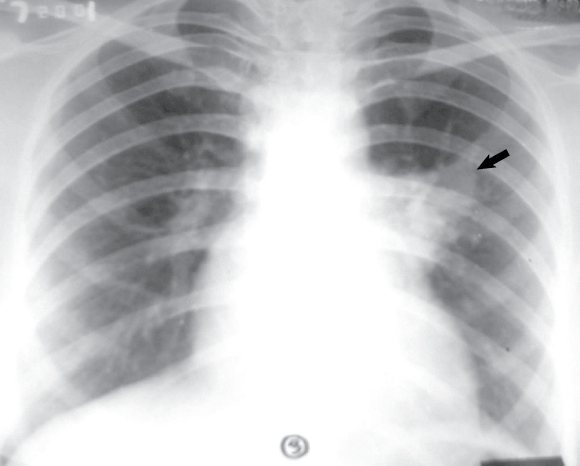

On examination, the patient had cyanosis and clubbing (Box 1), and a lumpy tongue (Box 2) suggestive of tongue telangiectasia. A chest x-ray showed left mid-zone opacity (Box 3), which was confirmed to be a pulmonary arteriovenous malformation (AVM) on spiral computed tomographic angiography (Box 4). Transcutaneous embolotherapy produced a marked improvement in her symptoms. The patient is currently asymptomatic and undergoing regular follow-up.